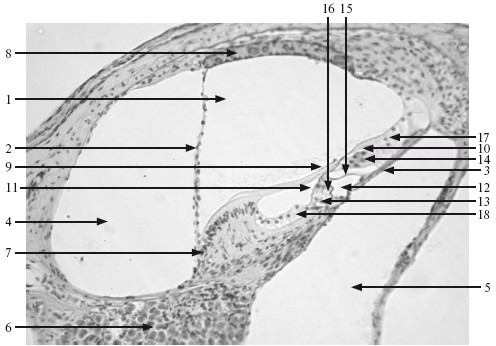

Рис. 10.3. Спиральный орган. х 210.

1 – перепончатый канал улитки; 2 – вестибулярная мембрана; 3 – базилярная пластинка; 4 – вестибулярная лестница; 5 – барабанная лестница; 6 – спиральный ганглий; 7 – спиральный гребень; 8 – сосудистая полоска; 9 – покровная мембрана; 10 – наружные волосковые клетки; 11 – внутренние волосковые клетки; 12 – туннель; 13 – внутренние поддерживающие клетки; 14 – наружные поддерживающие клетки; 15 – наружные клетки-столбы; 16 – внутренние клетки-столбы; 17 – наружные пограничные клетки; 18 – внутренние пограничные клетки.